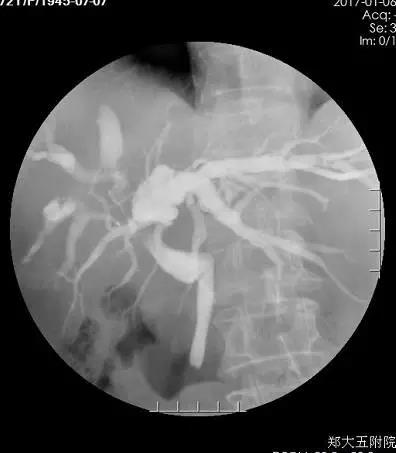

术后15天,樊奶奶做了经PTCD管给胆管造影,结果发现肝内外胆管已经通了。术后40天,樊奶奶又来院复查,她告诉李晓勇教授自己的食欲现在非常好,生活质量比以前明显提高。陈艳军副主任为樊奶奶复查了肿瘤标记物,结果发现肿瘤标志物已经完全恢复正常。

术后2周胆道造影